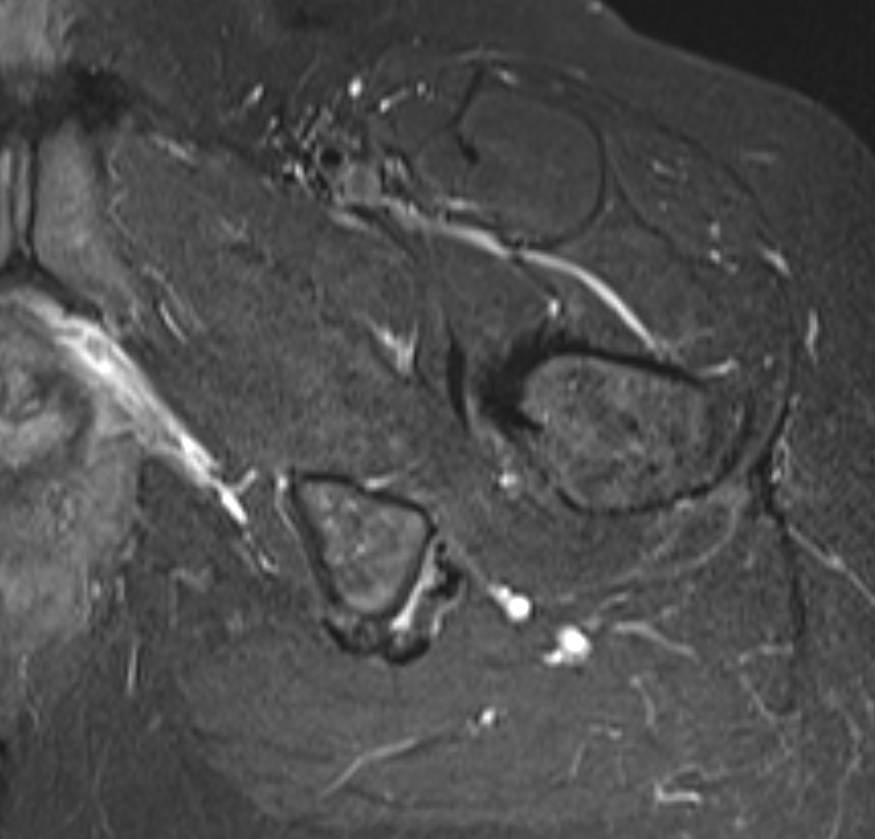

Proximal hamstring tear on right (red circle), normal insertion on tuberosity on left (blue circle)

Proximal hamstring avulsion on right - red circle is retracted hamstring tendon, blue circle is normal insertion on left

Proximal hamstring tear on right (red circle), normal insertion on left (blue circle)

Proximal hamstring avulsion, with tendon floating in hematoma / seroma